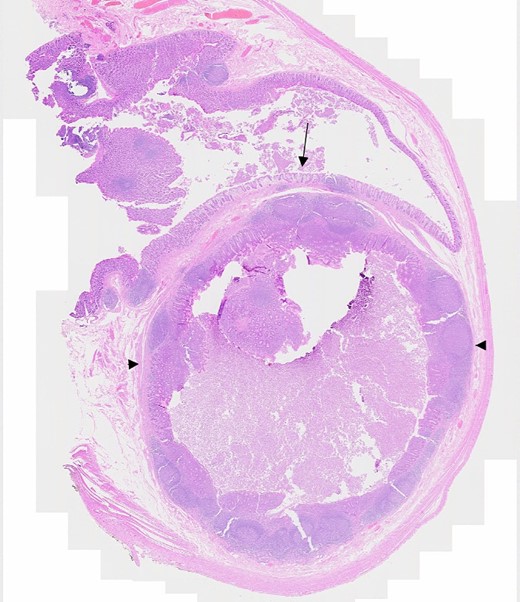

Microscopically (Fig. 3), sections of base of appendix and adjacent caecum showed a submucosal cystic lesion lined by large bowel mucosa with mucosal lymphoid follicle resembling appendiceal lining, in keeping with an appendiceal diverticulum at the base of appendix resembling a submucosal caecal lesion. Sections of the rest of appendix showed slight dilatation of the lumen with mildly inflamed mucosa, but were otherwise unremarkable. There was no evidence of dysplasia or malignancy.

Microscopic section showing appendiceal diverticulum, Arrow: Caecal mucosa, Arrowheads: Submucosal lesion.